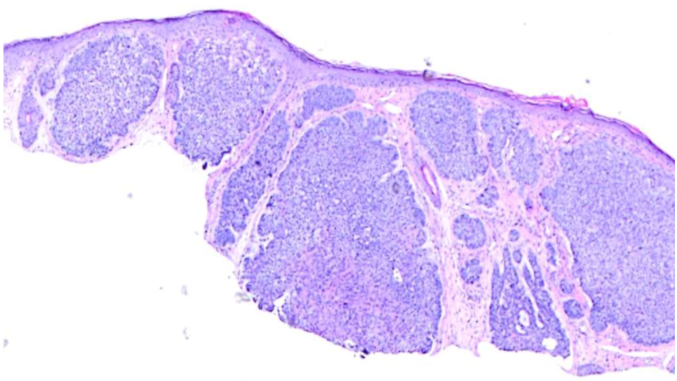

- They removed a section of skin, examined it under a microscope, and repeated the process until the margins were clear of cancer cells.